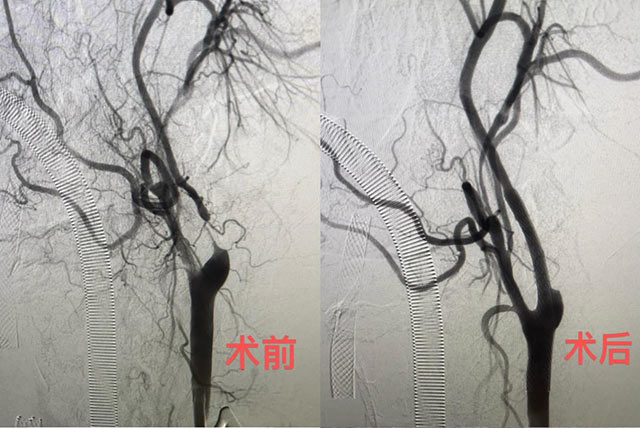

68岁的张伯(化名)因枕部头痛、耳鸣多次住院,被查出颈动脉重度狭窄。近日,广东省人民医院神经外科团队为张伯开展颈动脉狭窄治疗的全新术式:经颈动脉血运重建术(TCAR)。此前,该项技术在华南地区尚未见应用报道。术后张伯康复顺利,已经出院。

而TCAR是一种全新的、结合上述两种传统治疗方法优势的颈动脉介入治疗方法,将颈动脉显露与血流逆转相结合,以最大程度减少栓塞发生的可能性。

“新术式是经颈动脉的血流运输重建。说得简单点,我们在体外接一条人工血管,从颈动脉接到股静脉,体外血管里会放上一个特别密的保护网,能兜住绝大部分脱落的斑块栓子。这样我们在放球囊扩张血管时,就不用太担心血栓脱落流到脑血管里的问题。”陈光忠表示,采用这种技术后,栓塞的可能性就变得非常低。

陈光忠介绍,TCAR具有小伤口、微创、不经过主动脉弓、神经损伤几率低等优势,30天围手术期总卒中发生率低至1.4%(传统术式的发生率约为5%),让颈动脉狭窄的治疗更加安全有效。